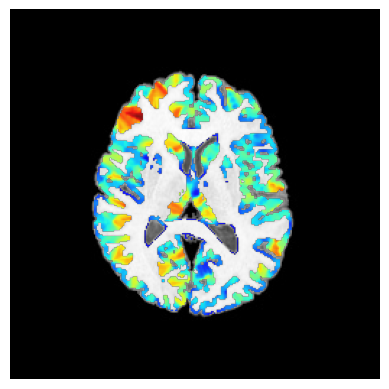

2025-12-22 09:10:36 | INFO | nipype.workflow | [Node] Executing "synthstrip" <mriqc.interfaces.synthstrip.SynthStrip>

2025-12-22 09:10:36 | INFO | nipype.workflow | [Node] Executing "_averages1" <mriqc.interfaces.diffusion.WeightedStat>

2025-12-22 09:10:37 | INFO | nipype.workflow | [Node] Finished "_tpms_std2t1w0", elapsed time 10.619959s.

2025-12-22 09:10:37 | INFO | nipype.workflow | [Node] Finished "_tpms_std2t1w1", elapsed time 10.979466s.